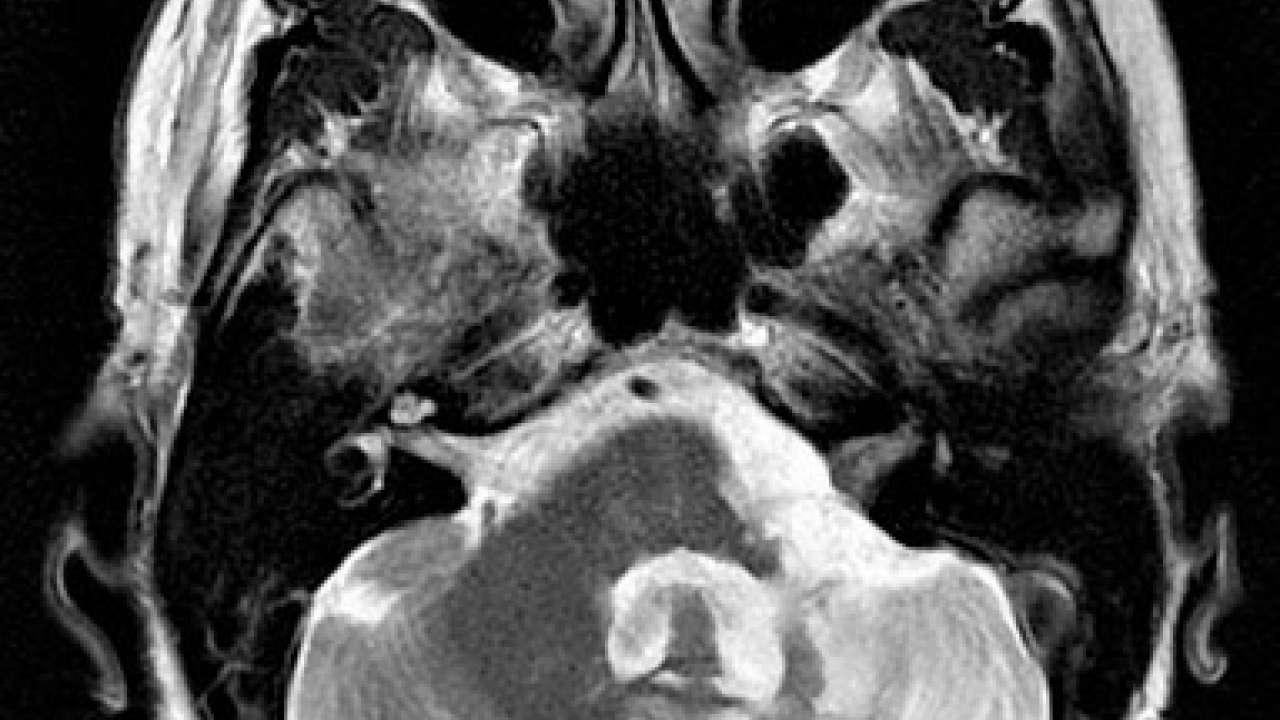

Small acoustic neuroma (11 × 6 mm). Download Scientific Diagram Acoustic Neuroma Ucla An acoustic neuroma is a tumor found in the area of the brain where the auditory (hearing) nerve enters the bony opening of the skull between. Removing acoustic neuromas is challenging because of their location. Vestibular schwannomas (vs), historically known as acoustic neuromas, are benign neoplasms arising from schwann cells surrounding the. It grows slowly from an overproduction of schwann. Acoustic Neuroma Ucla.

MRI Showing intracannalicular extention of Acoustic neuroma. Download Acoustic Neuroma Ucla Also includes information on an research. Information about current acoustic neuroma medical studies and trials which acoustic neuroma patients or caregivers may participate in. Removing acoustic neuromas is challenging because of their location. Acoustic neuroma is a rare noncancerous tumor. Acoustic neuroma surgery can be risky. Vestibular schwannomas (vs), historically known as acoustic neuromas, are benign neoplasms arising from schwann. Acoustic Neuroma Ucla.

Acoustic neuroma with obstructive hydrocephalus Image Acoustic Neuroma Ucla Acoustic neuroma surgery can be risky. It grows slowly from an overproduction of schwann cells and is also called a vestibular schwannoma. Removing acoustic neuromas is challenging because of their location. Vestibular schwannomas (vs), historically known as acoustic neuromas, are benign neoplasms arising from schwann cells surrounding the. Acoustic neuroma is a rare noncancerous tumor. Information about current acoustic neuroma. Acoustic Neuroma Ucla.